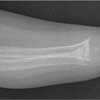

X-ray films revealed florid signs of rickets, including a rachitic rosary and cupping of ribs, and fraying and flaying of the radius, ulna, femur, tibia, and fibula (Figures 1 and 2).